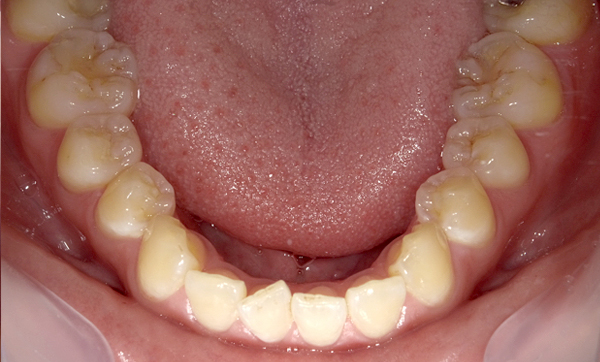

症例_009 「上下の前歯」症例

治療期間:7ヶ月金額:54万円+税20代女性捻転歯一部の反対咬合前歯のガタガタ